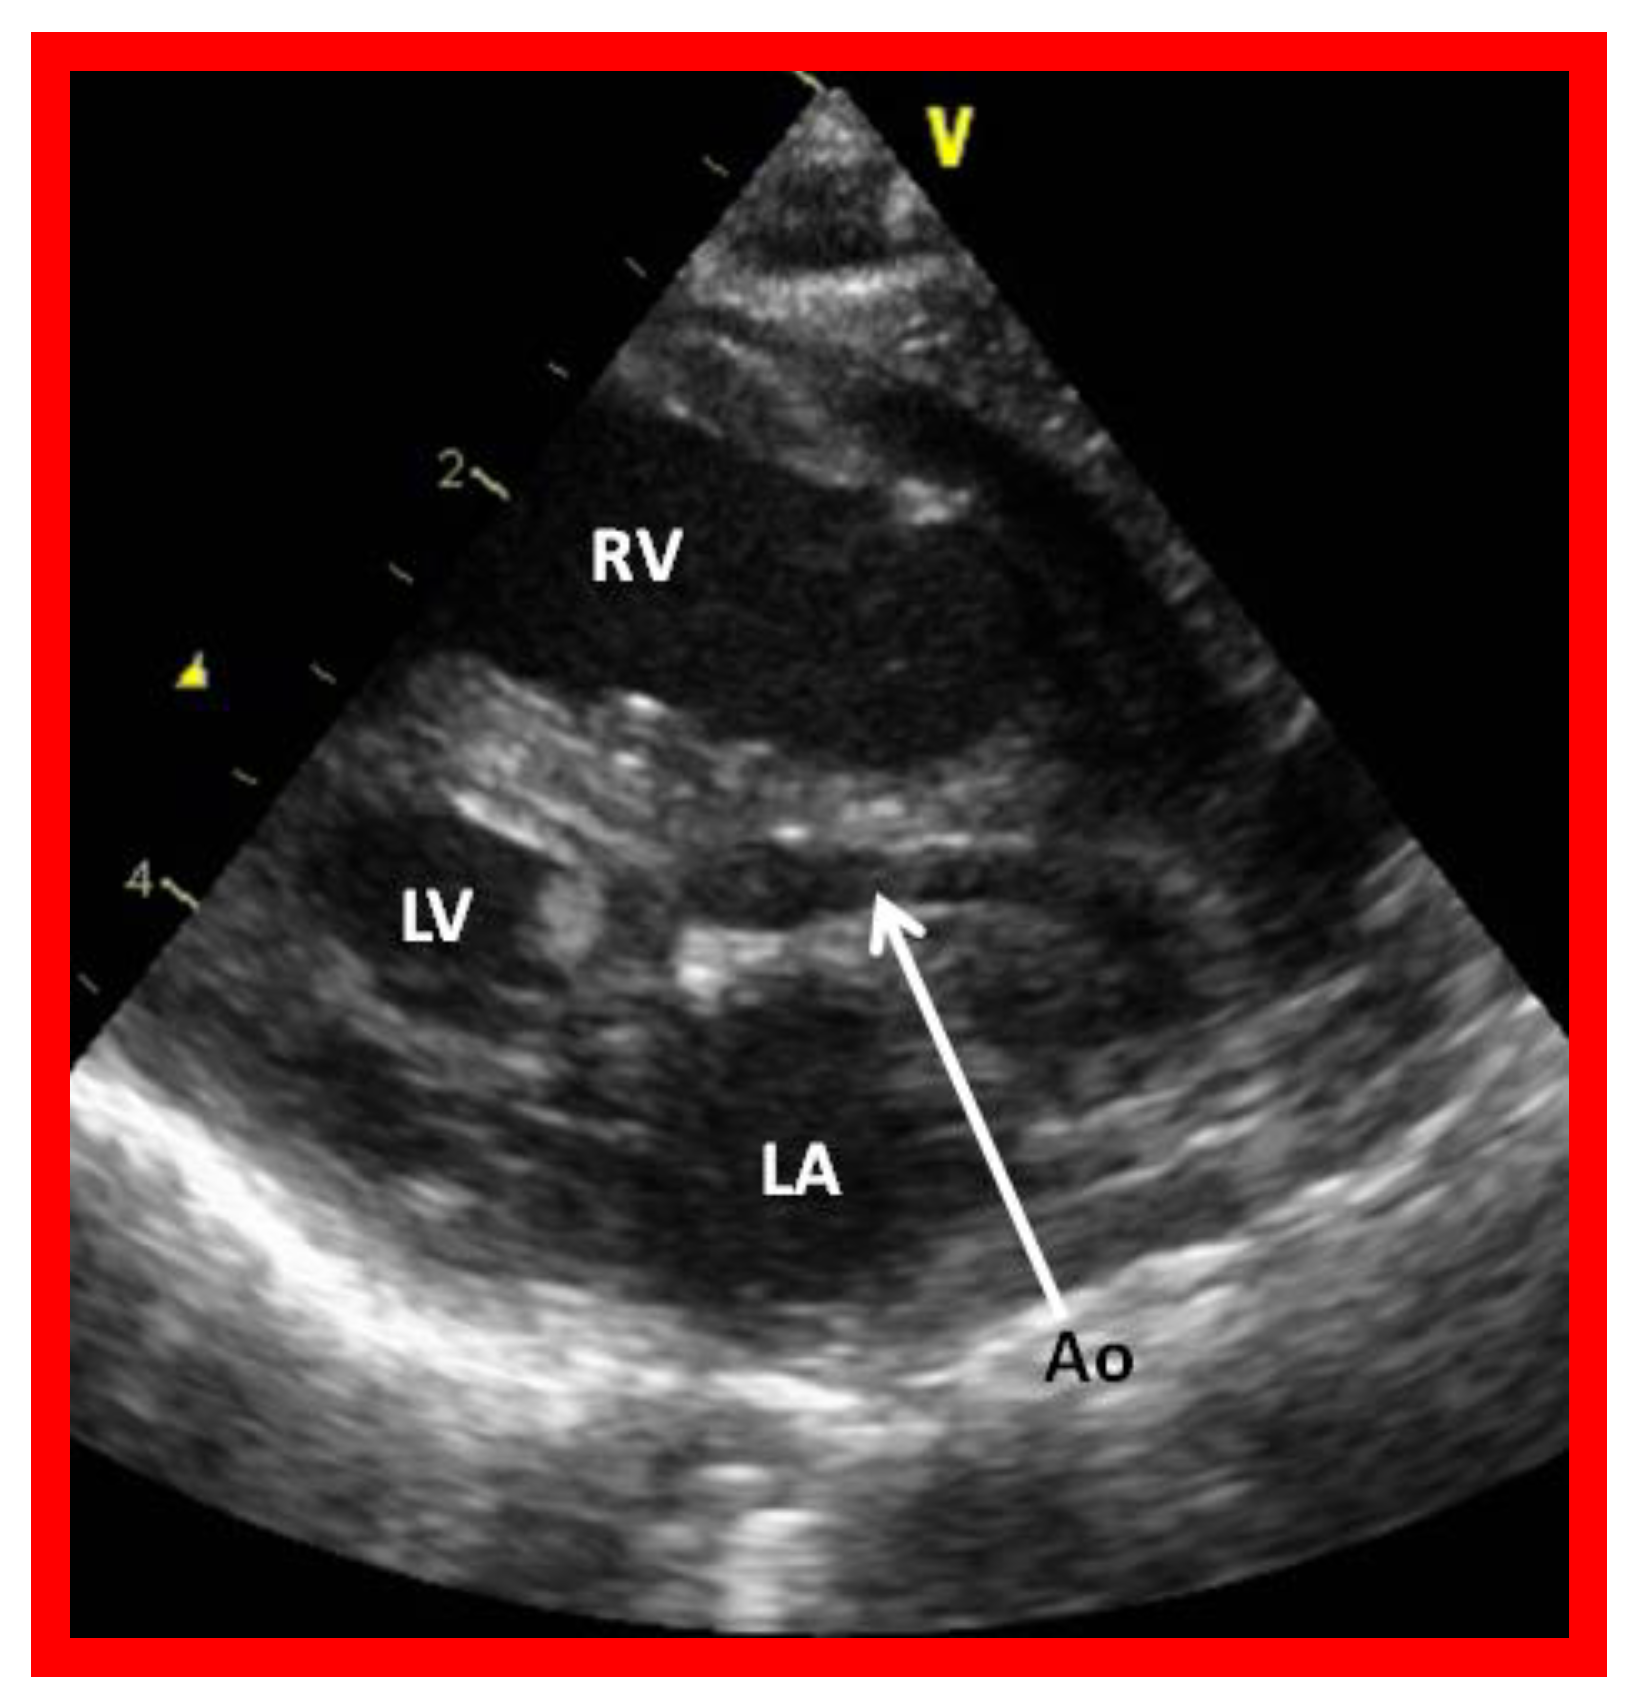

2.3. Double-Inlet Left Ventricle